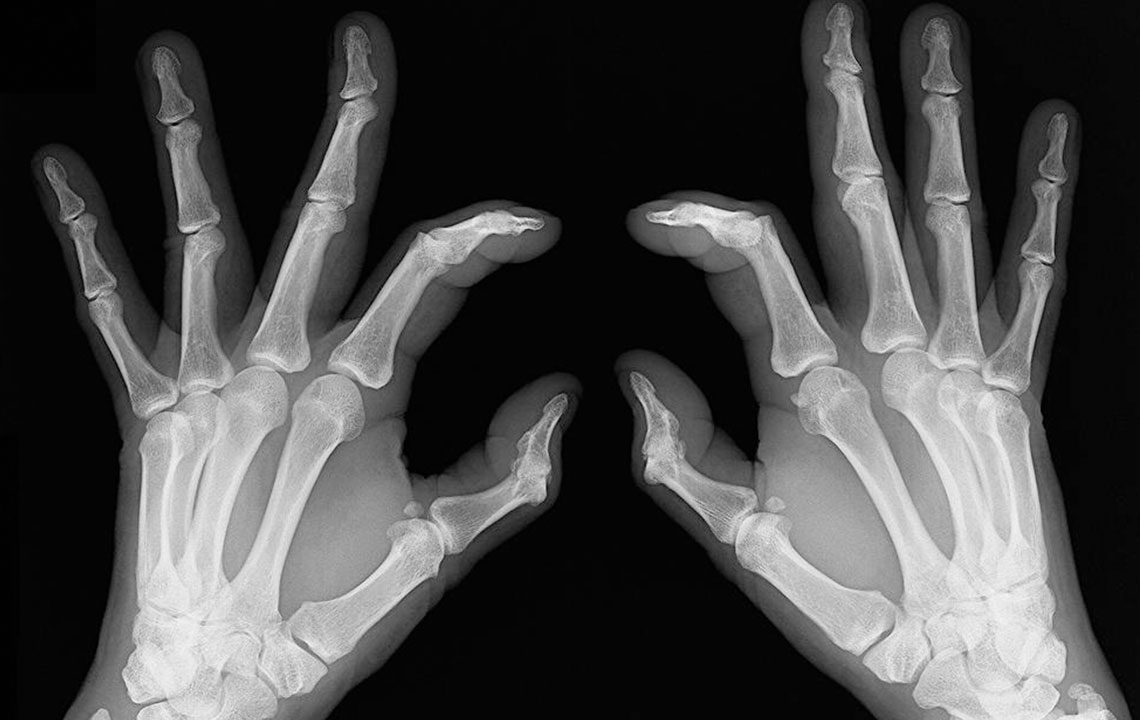

It is these similarities that cause a lot of confusion with the diagnosis of rheumatoid arthritis and lupus. There are several times when patients are diagnosed with rheumatoid arthritis when they actually have lupus. This usually happens in the early stages of the disorder. As the condition progresses, the difference becomes evident; rheumatoid arthritis causes bone deformity and erosion while lupus rarely leads to bone erosion.